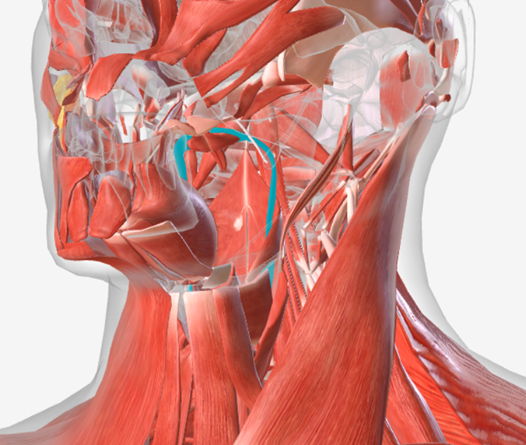

Stylopharyngeus

origin is the styloid process, coursing down to insert into the pharyngeal constrictors and the posterior thyroid cartilage; function is to elevate and open the pharynx

Stylopharyngeus

A

Styloglossus

B

Stylohyoid

C